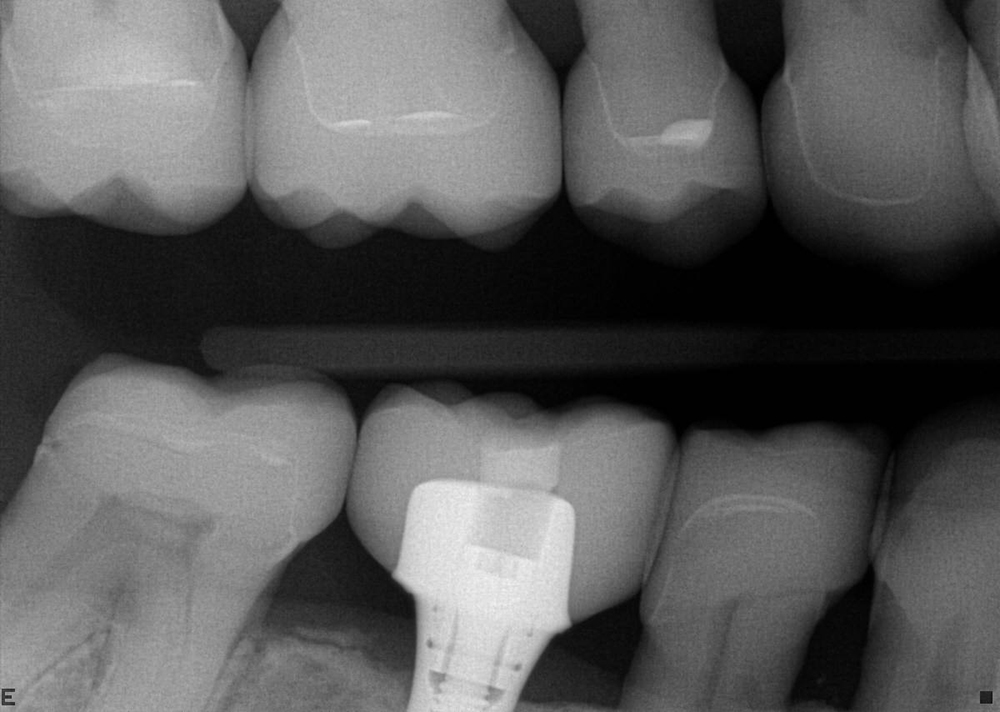

Full Mouth Radiographic Series, Maxillary and Mandibular Intraoral Scans, Digital Jaw Relation Recording with a Leaf Gauge, Complete Photographic Series, Periodontal Charting, Restorative Charting.